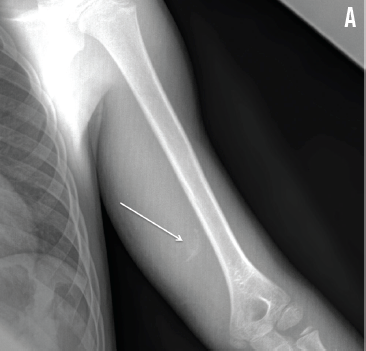

Michele Lossius, MD; Iain Elliott, MD

A previously healthy 8-year-old boy presented after having injured his left arm while playing football 2 weeks prior. Radiographs obtained at that time showed no fractures.